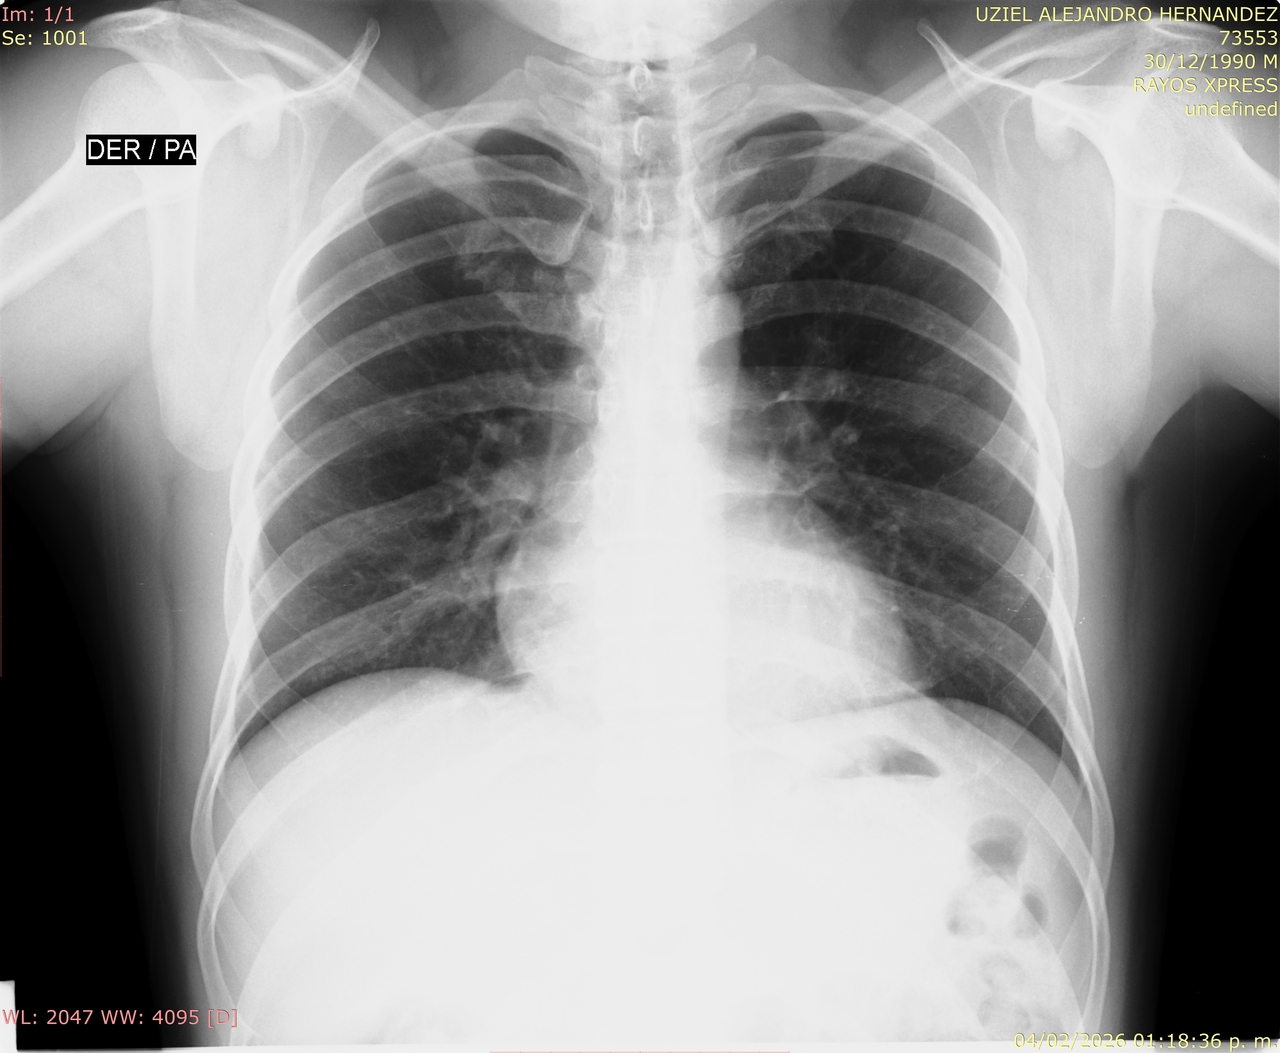

estudios de gabinete

Un medico general evalúa la salud del candidato revisando sus resultados de exámenes de laboratorio y estudios de gabinete asi como sus antecedentes médicos.